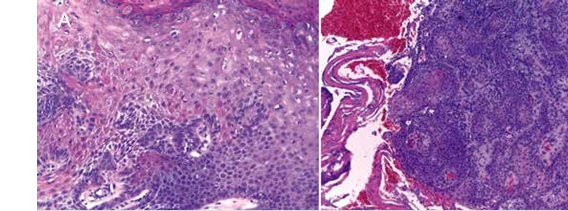

Bajo el diagnóstico clínico de queilitis actínica y alta sospecha de CCE se le realizaron dos biopsias incisionales del bermellón inferior. El análisis histopatológico reveló en una de las muestras queilitis actínica con displasia leve (Figura 6A) y en la otra carcinoma de células escamosas muy bien diferenciado (Figura 6B).